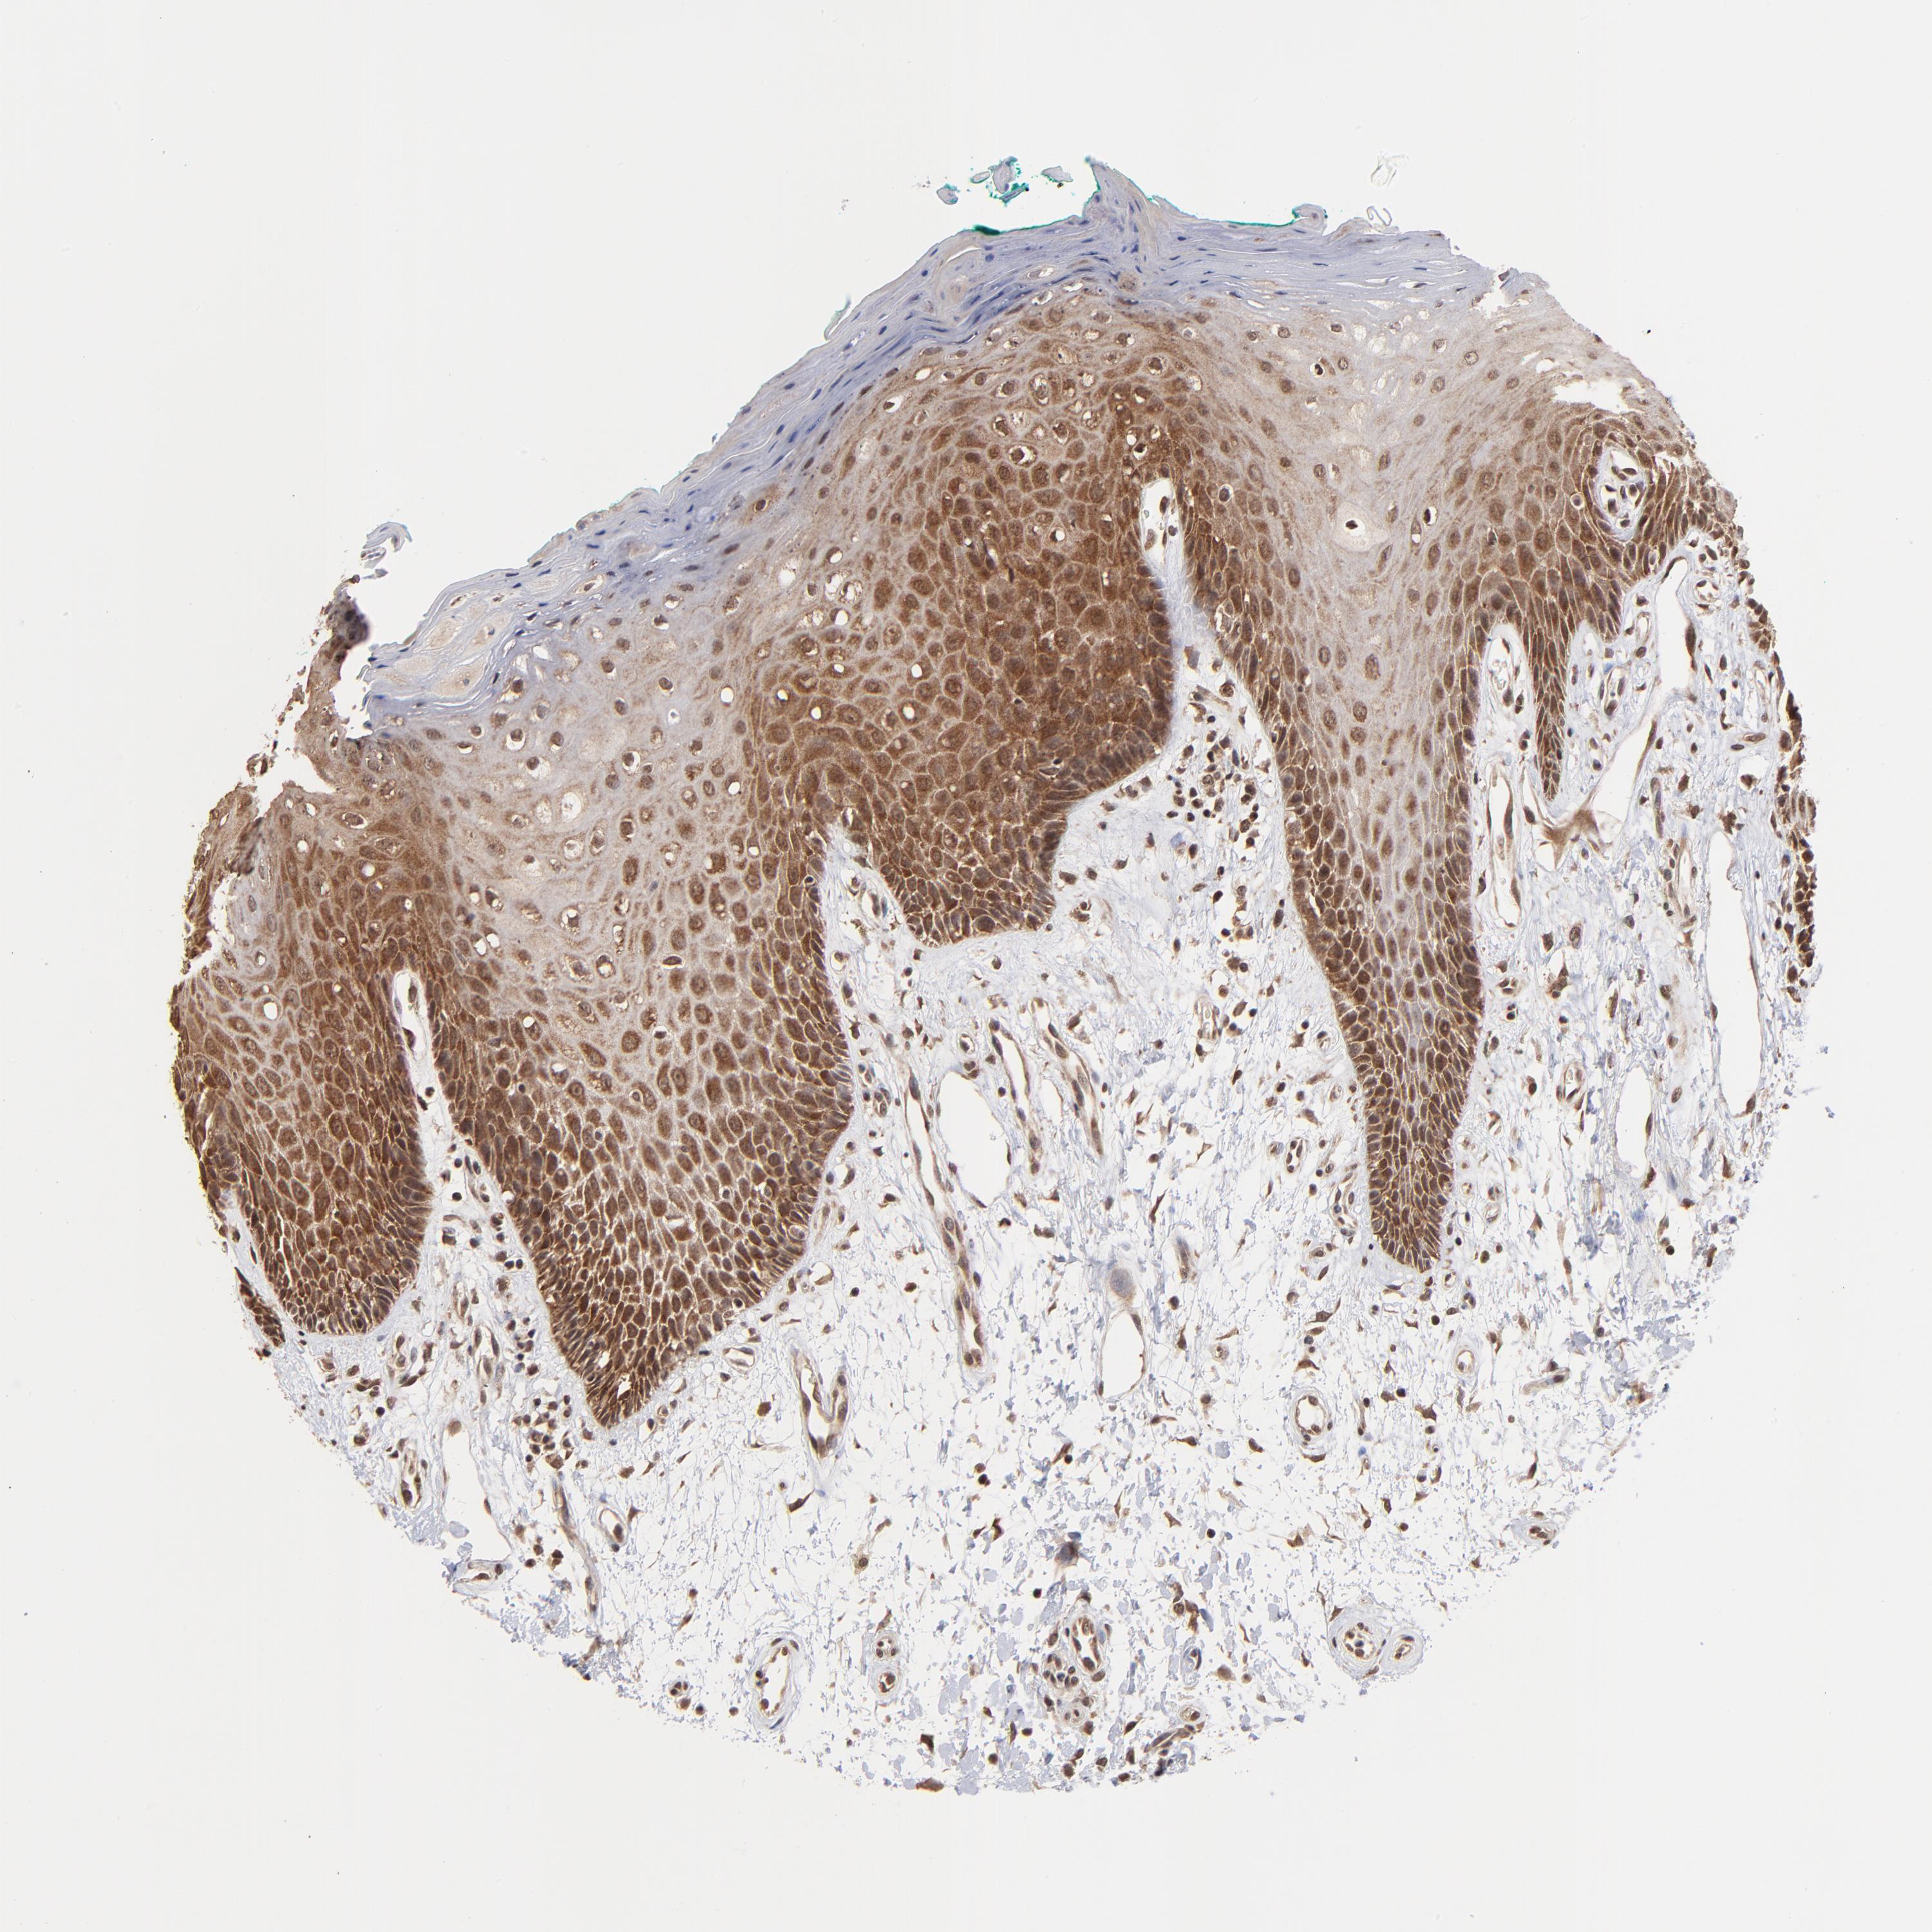

BRPF1